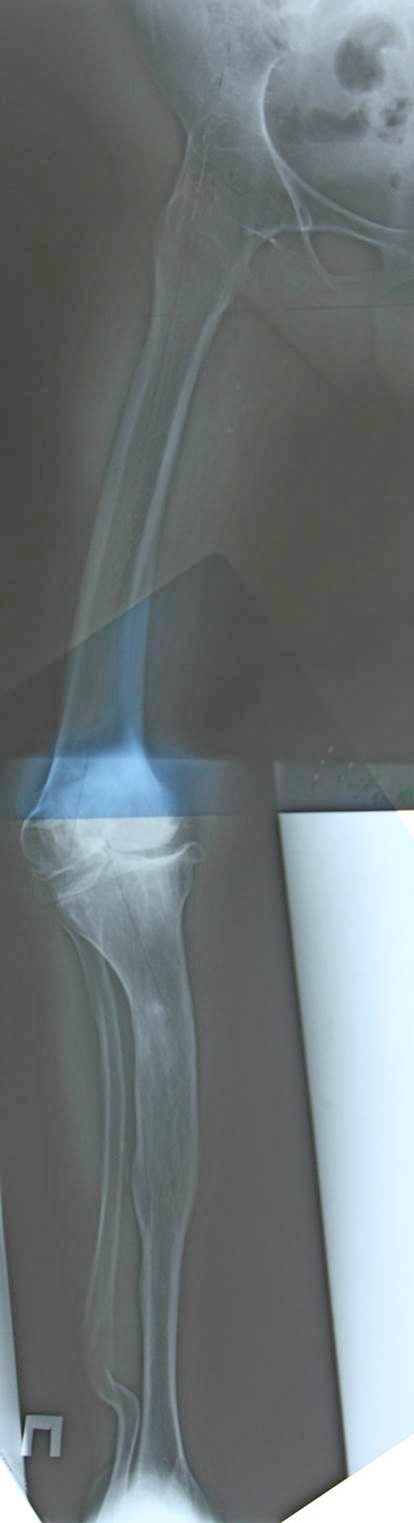

В аттаче первичном почему-то темный снимок. Выкладываю поярче.

Артродез тазобедренного сустава неизвестной давности и сложная компенсаторная деформация конечности. Для принятия решения одной проекции не хватает. Дополнительно: общий таз и на всю длину конечности рентгенорамма с включением голеностопного. Отдельные снимки тазобедренного и коленного суставов.

Джолдас, спасибо за совет. Боковые проекции, конечно же, есть, но на них, скажем так, ничего примечательного. Равно как и таз с эндопротезом левого тазобедренного, который стоит весьма анатомично. В целом я тоже склоняюсь к тому, что никакие корригирующие остеотомии не нужны - они только помешают. Центр ротации правого тазобедренного сустава у нее где-то в позвоночнике и? как один из вариантов, планируется поставить обычные бедро и тибию ориентируя как раз на позвоночник.

В общем было решено выполнить обычное эндопротезирование. Навигатор нашел точку ротации где-то в позвоночнике, на нее и ориентировались.

Снимки ниже.

Оперировал Проф. Мурылев В.Ю., асс. Рукин Я.А., Середа А.П.

Будем следить. Большое спасибо за советы.